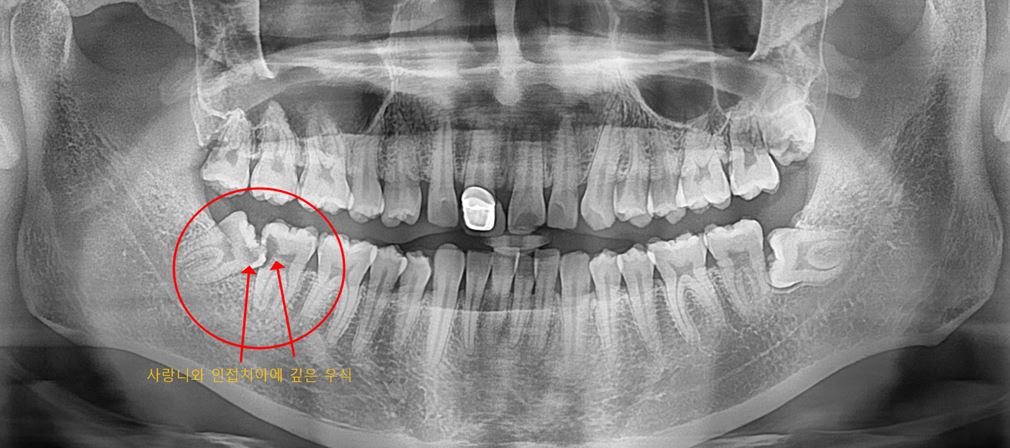

[치료 전 파노라마]

매복 사랑니가 일부 노출된 경우 음시굴이 잘 끼고 치아 우식 발생 가능성이 높습니다.

실제로 파노라마 사진 보면 사랑니와 인접치아사이에 깊은 우식이 있는 상태였습니다.